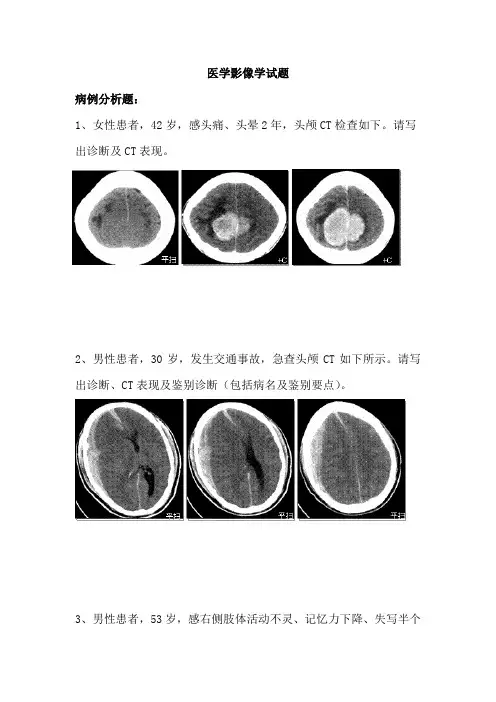

医学影像学试题病例分析题:1、女性患者,42岁,感头痛、头晕2年,头颅CT检查如下。

请写出诊断及CT表现。

2、男性患者,30岁,发生交通事故,急查头颅CT如下所示。

请写出诊断、CT表现及鉴别诊断(包括病名及鉴别要点)。

3、男性患者,53岁,感右侧肢体活动不灵、记忆力下降、失写半个月,MRI检查如下,请写出诊断、MRI表现及鉴别诊断(包括病名及鉴别要点)。

参考答案1、脑膜瘤。

CT表现:①双侧顶区矢状窦旁可见半球形病灶,广基底与大脑镰相连;②平扫呈一较高密度病灶,边界清楚;③增强后病灶明显均匀强化;病灶周围可见低密度的水肿区,无强化。

2、额、颞、枕、顶急性硬膜下血肿合并蛛网膜下腔出血。